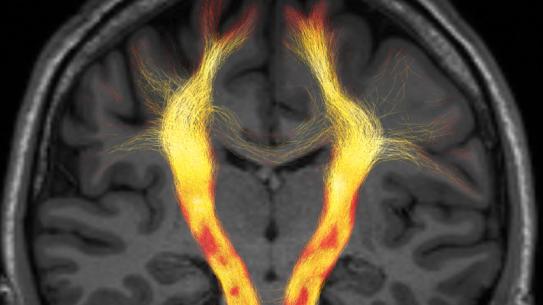

MRI Biophysics Group Professor Els Fieremans works on validation methods for diffusion magnetic resonance imaging (MRI) including hardware, numerical phantoms, a...